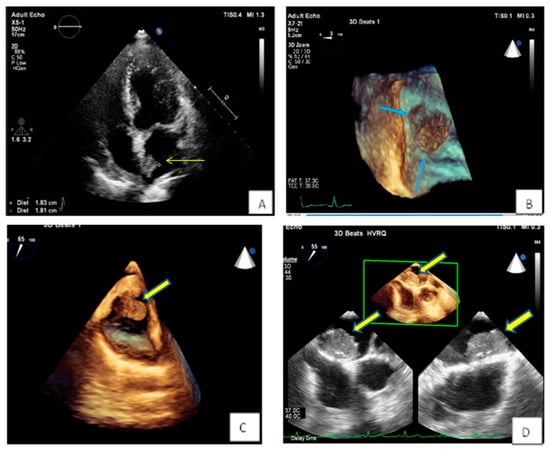

3.1. Transthoracic Echocardiography

- Zaragosa-Macias, E.; Chen, M.A.; Gill, E.A. Real time three-dimensional echocardiography evaluation of intracardiac masses. Echocardiography 2012, 29, 207–219. [Google Scholar] [CrossRef] [PubMed]

- Aggeli, C.; Poulidakis, E.; Felekos, I.; Aggeli, A.; Stefanadis, C. An octopus-like myxoma depicted by real-time 3D transesophageal echocardiography. Hell. J. Cardiol. 2012, 53, 470–471. [Google Scholar]